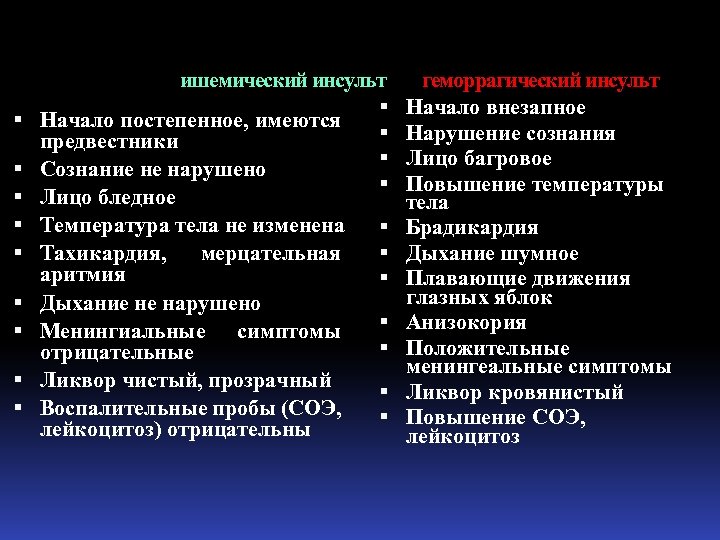

ишемический инсульт геморрагический инсульт Начало внезапное Начало постепенное, имеются Нарушение сознания предвестники Лицо багровое Сознание не нарушено Повышение температуры Лицо бледное тела Температура тела не изменена Брадикардия Тахикардия, мерцательная Дыхание шумное аритмия Плавающие движения глазных яблок Дыхание не нарушено Менингиальные симптомы Анизокория Положительные отрицательные менингеальные симптомы Ликвор чистый, прозрачный Ликвор кровянистый Воспалительные пробы (СОЭ, Повышение СОЭ, лейкоцитоз) отрицательны лейкоцитоз

ишемический инсульт геморрагический инсульт Начало внезапное Начало постепенное, имеются Нарушение сознания предвестники Лицо багровое Сознание не нарушено Повышение температуры Лицо бледное тела Температура тела не изменена Брадикардия Тахикардия, мерцательная Дыхание шумное аритмия Плавающие движения глазных яблок Дыхание не нарушено Менингиальные симптомы Анизокория Положительные отрицательные менингеальные симптомы Ликвор чистый, прозрачный Ликвор кровянистый Воспалительные пробы (СОЭ, Повышение СОЭ, лейкоцитоз) отрицательны лейкоцитоз